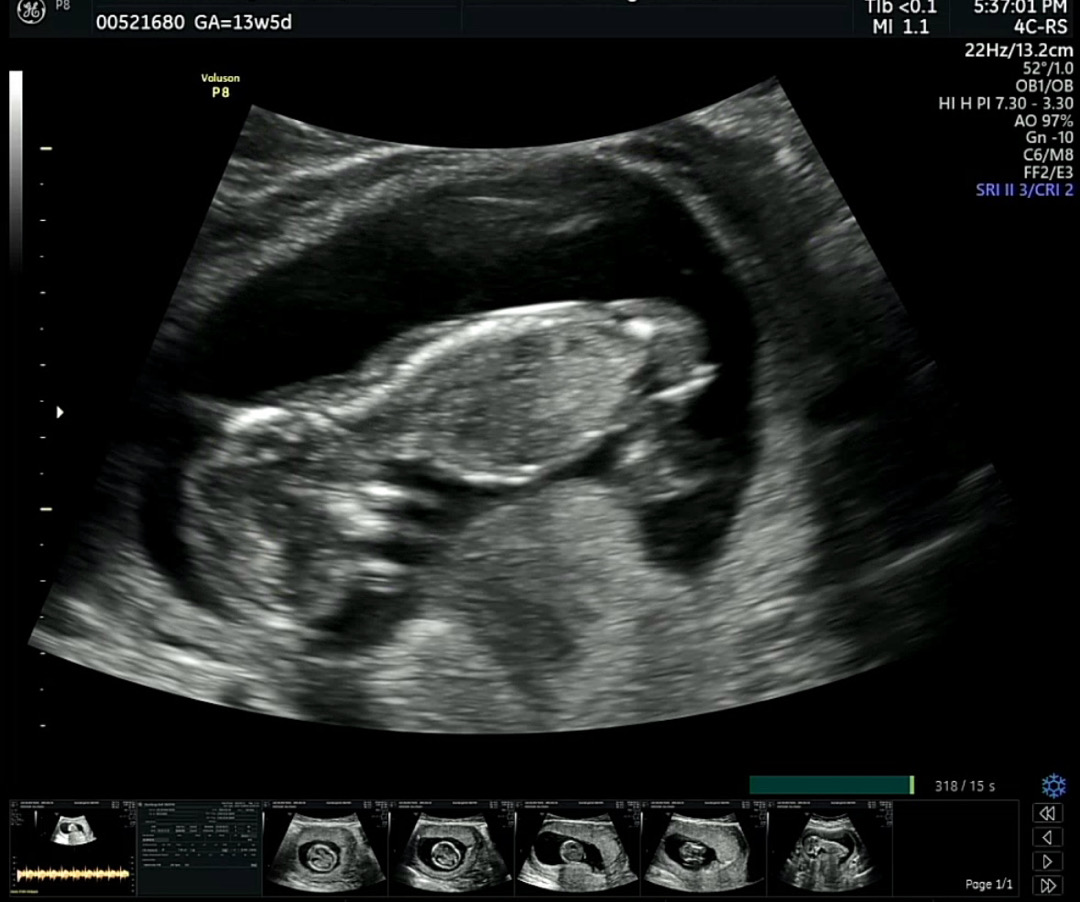

13주5일차 각도법봐주세용🙏

의사쌤이 각도법으로 알수있게찍어주셨다고만 말씀해주셨는데요. 제가 잘볼 줄 몰라서요! 혹시 딸인가용?! 아시는분 있으면 댓글부탁드립니당☺️☺️

근데 각도법이 초음파보는 방향이랑 각도도 달라서요ㅠ지인은 딱 저랬고 유명한 ㅈㄲㅁ님도 딸한표주셨는데 아들이었어용